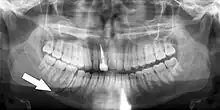

Essa lesão envolve o osso alveolar e pode se estender além do alvéolo. [7] [8] Existem 5 tipos diferentes de fraturas alveolares:

Sinais de fratura dento-alveolar:

- Elementos dentários movendo-se juntos como um segmento e normalmente são deslocados.

- Hematomas na gengiva inserida.

- Gengiva em toda a linha de fratura frequentemente lacerada[9].

Investigação: Requer mais de uma visualização radiográfica para identificar a linha de fratura.

Tratamento: Reposicionar os dentes deslocados sob anestesia local e estabilizar o segmento móvel com uma tala por quatro semanas; suturar quaisquer lacerações de partes moles.